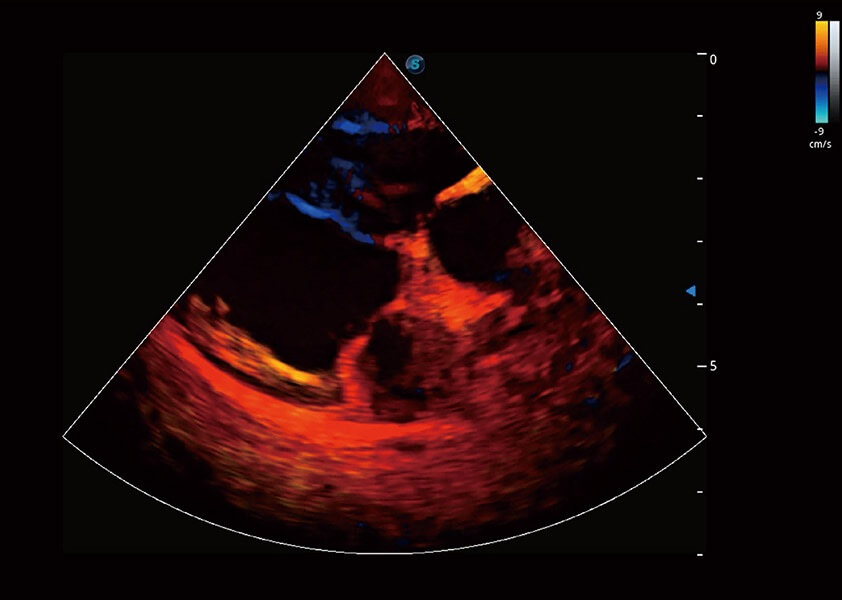

ProPet 60 作为一款高端台式动物超声设备,为动物医生的日常诊断提供了一系列贴合动物临床需求、解决临床实际问题的高级成像功能。凭借全系列高清探头,满足医生对腹部、心脏、生殖、浅表、肌骨等成像的所有需求,切实帮助您提升检查效率,提高诊断信心。

动物是人类最亲密的朋友和最值得信赖的伙伴。亚星官网也一直致力于探索动物专用的超声影像解决方案。 全新推出的ProPet系列,是亚星官网在动物超声影像智能化、专业化、精准化的一次跨越式革新。动物不能用言语来表述自己的不适,通过超声影像,ProPet系列搭建了动物医生与不同物种沟通的“桥梁”,为动物医生注入了“治愈之力”。